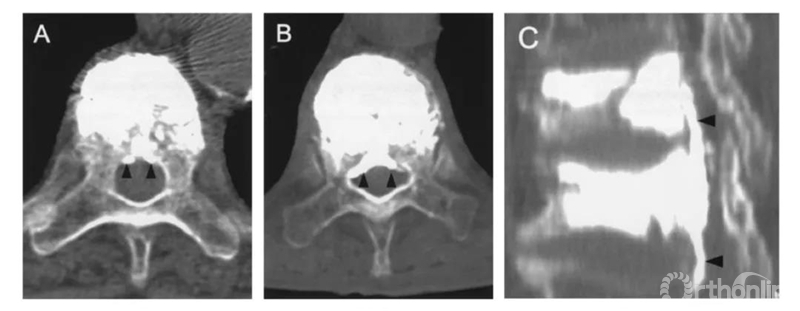

根据渗漏的途径及CT表现,将骨水泥渗漏分为三种类型:B经椎旁静脉渗漏;S经节段血管渗漏;C经皮质缺损渗漏。

B经椎旁静脉渗漏:在椎体后缘相对对称分布。一般不超过椎管横径的1/3。矢状位CT显示会向头尾侧弥散。

S经节段血管渗漏:沿节段静脉走行弥散。轴位CT呈水平走行。有时会顺着血管上下弥散,矢状面呈垂直或斜行。

C经皮质缺损渗漏:顺着缺损区到处跑,椎体周围、椎管内、椎间盘,哪里有路往哪走。

术中用C臂判断渗漏的准确率低的可怜。

只照侧位,大约30%的准确率。

正侧位都看,准确率也不过50%左右。

对于部分特殊部位渗漏,准确率更只有7%。

比如这例,侧位X片看骨水泥在椎弓根里,可CT一扫发现已经渗漏进入椎管。

侧位X片看骨水泥在椎体里,CT显示渗漏进入椎管。

侧位X片看骨水泥在椎间孔周缘,CT显示渗漏进入椎管,累及椎间孔。

术中打骨水泥时多问问患者,如果出现不适,哪怕C臂看着没问题,也赶紧停下来,安全第一。说不定已经漏到神经周围了只是C臂没看出来。术后及时复查三维CT。